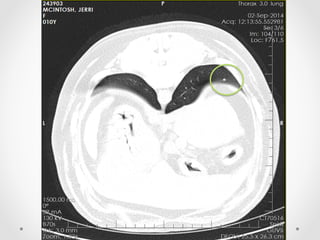

• 12.

Diagnostic imaging dx: Largeaggressive soft tissue lesion with invasion and destruction of proximal left ulna - likely neoplastic. CT  forelimbs  (bone  &  soft  tissue  windows)

Considerations •  Tried simulatinga left forelimb amputation by bandaging it up •  The worrying CT scan findings o  Pulmonary metastases – prognosis slightly poorer (though early stage metastatic disease as not detected on radiography yet) o  Compromised right elbow – arthritic change + possible neoplasm as well